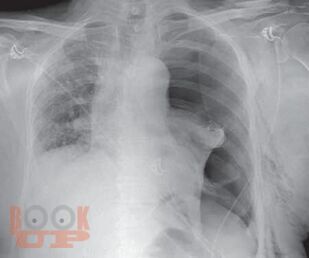

First textbook about pleural disease written and edited by Indian authors. First pleural textbook which has contributions from multiple authors. Textbook of pleural disease which has been authored by multiple specialtiesa unique feature where each chapter has been written by the concerned specialists, e.g., pleural disease in kidney disease by nephrologist, hepatic hydrothorax by hepatologist, and pleural disease in gynecological disorder by gynecologist. Every aspect of pleura from embryology, anatomy, physiology, and radiological diagnosis has been covered in detail. Role of ultrasonography in pleura, which is now a vital tool for point-of-care management has been described in detail. High-quality pleural imaging and its highlights are shown in concerned chapters Pathophysiologic basis of pleural diseases has been discussed with each specific disease. Concise algorithm summarizing disease management has been clearly depicted. Updated treatment as per recent guidelines has been incorporated. The topics in pleural diseases have been written by eminent chest physicians all over India. A special chapter describes pleural diseases in COVID, in the post pandemic era. Being a Lung Transplant center, a special chapter on overview on pleura issues in lung transplant has been elaborated.